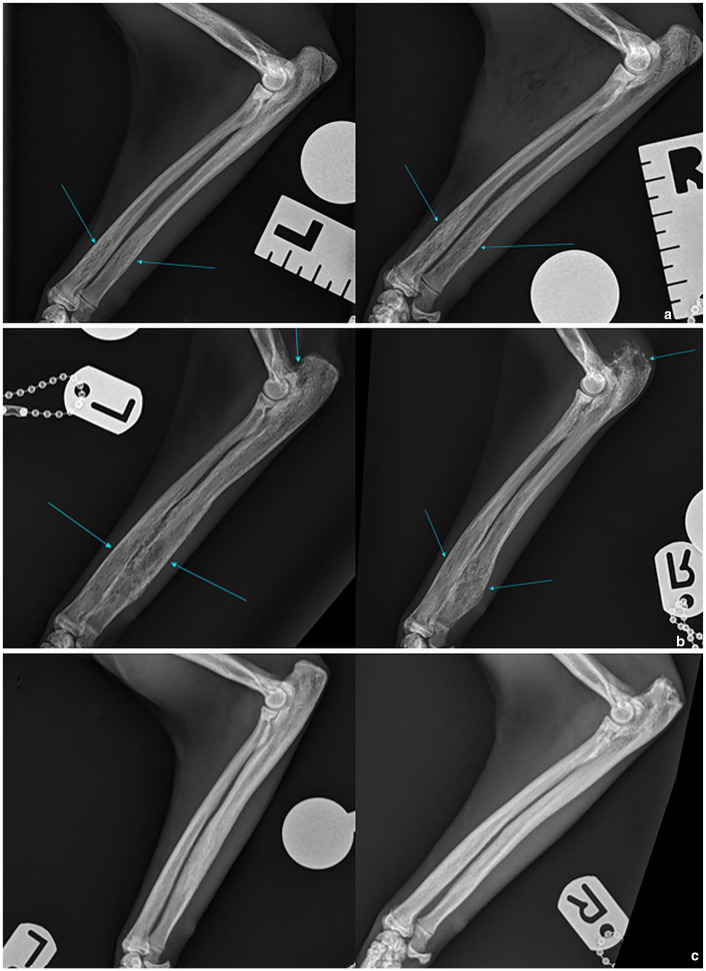

Case summary: A 1-year-old male castrated Savannah cat presented with chronic recurrent lethargy, stiffness, right pelvic limb lameness and spinal hyperaesthesia. Eight months before referral, the cat was treated with prednisolone, remdesivir and a 1-week course of amoxicillin/clavulanic acid and marbofloxacin for suspected feline infectious peritonitis. Multiple recurrences were reported after initial presentation, and were treated with 1-week courses of amoxicillin/clavulanic acid. Neurological examination did not reveal further findings. Haematology showed neutrophilia/monocytosis. Spinal, limb and thoracic radiographs revealed irregular endplates and narrowing of T12-T13 and L7-S1 intervertebral disc spaces, metaphyseal lesions of multiple long bones with heterogeneous medullary bone and reduced corticomedullary distinction, and two areas of increased opacity in the left lung lobes. Feline leukaemia virus, feline immunodeficiency virus, toxoplasma serology and urine culture were negative. Blood culture was positive for Salmonella species. Amoxicillin/clavulanic acid (20 mg/kg q12h) was started with clinical improvement, but no resolution of haematological/imaging changes. Relapse occurred 7 months into treatment. Blood culture showed Phocaeicola massiliensis, a suspected contaminant. Metronidazole (11 mg/kg q12h) was added based on sensitivity, with clinical improvement but relapse after discontinuation 4 months later. Neutrophilia and monocytosis were again identified, alongside hyperproteinaemia and globulinaemia. Recheck radiographs showed a worsening of the osteomyelitis but an improvement of the discospondylitis. Salmonella species were cultured again from blood and bone biopsies. Marbofloxacin (4.5 mg/kg q24h) was initiated. At the 6-month follow-up, complete resolution of clinical and laboratory findings was documented alongside radiographic improvement of the previous lesions. Treatment was discontinued with no relapses over the 10-month follow-up.